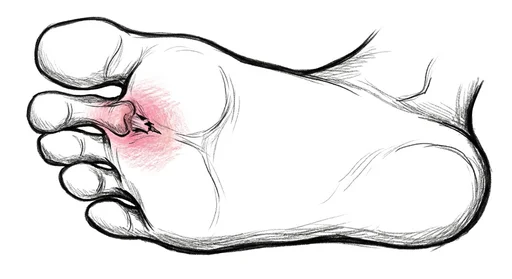

Foot & Ankle Exercise Guide

Choose your condition below to get started with exercises and stretches designed by Dr. Patish.

Pick your condition below, and you'll find your personalized exercise program — with medical illustrations, step-by-step instructions at three intensity levels, and clear guidance on when to call our office. Every protocol here is the same one Dr. Patish prescribes to patients in the clinic.

Forefoot & Toes